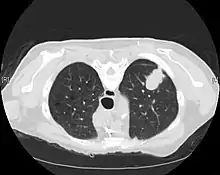

CT imaging provides better evaluation of the lungs, with higher sensitivity and specificity for lung cancer compared to chest radiograph (although still significant false positive rate[27]). Computed tomography (CT) that is specifically aimed at evaluating lung cancer includes the chest and the upper abdomen. This allows for evaluation of other relevant anatomic structures such as nearby lymph nodes, adrenal glands, liver, and bones which may show evidence of metastatic spread of disease.[4] Indeed, the US Preventative Services Task Force recommends annual screening with low-dose CT in adults aged 55 to 80 years who have a 30 pack-year smoking history and currently smoke or have quit within the past 15 years, with certain caveats (see Lung cancer screening).[28]